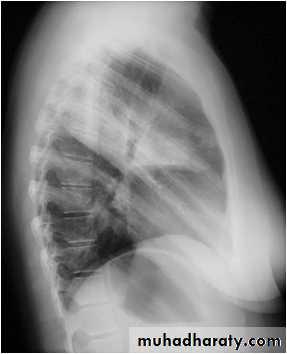

Right middle lobe collapse has distinctive features, and is usually relatively easily identified.

Radiographic features

Chest radiograph

Frontal chest XR showing opasity cause obscuration of the RT cardiac border

Lateral chest XR film the opacity is tongue like shape

versus (triangular in shape) in RT middle lobe consolidation seen in lateral chest XR film